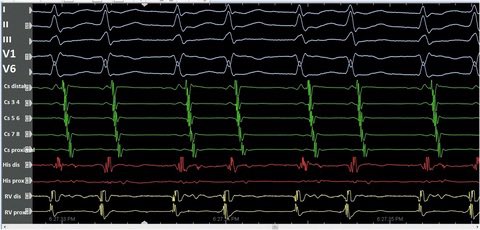

An unstable VT.

Mappable with #StaMP.

Guided by S3 Protocol.